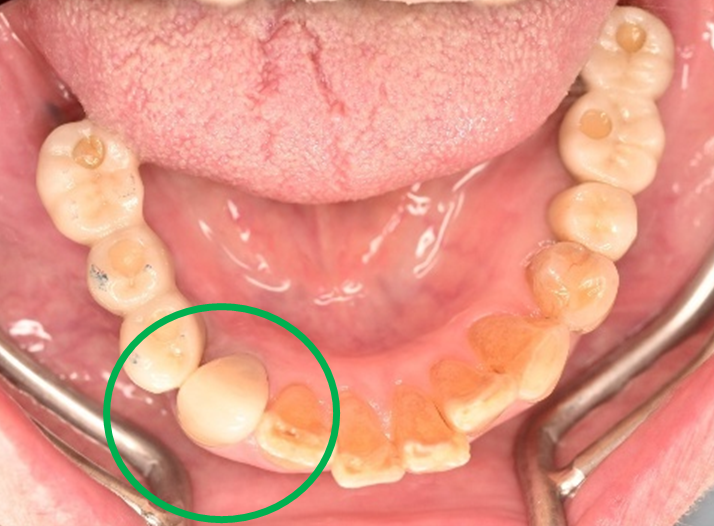

女性Yさん 60代(オールセラミック冠)

主訴

以前治療した右下の犬歯が、虫歯になり色が変わってきているので、治したい。

治療内容

根管治療をし、オールセラミック冠を被せました。

所感

神経が取り除かれ、歯自体が変色し、虫歯になっていました。根管治療をし、ファイバーコアを入れ、オールセラミック冠を被せました。

オールセラミック冠(失活歯)1本:¥104,500(税込)

Before

After